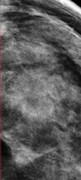

Dottor Catania,

secondo lei in questa mammografia di un anno fa erano presenti microcalcificazioni? Ingrandendo mi sembra di vedere in alto dei puntini...ma mi sa che li vedo perché li voglio vedere.. nella speranza che mi dicano che già c'erano e che non devo rifare tra 6 mesi un'altra mammografia...

Grazie

Ciarlina78

intendo questi puntini che vedo...